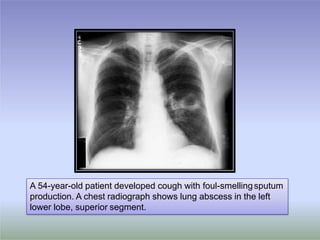

A 54-year-old patient developed cough with foul-smellingsputum

production. A chest radiograph shows lung abscess in the left

lower lobe, superior segment.

A 54-year-old patientdeveloped cough with foul-smellingsputum production. A chest radiograph shows lung abscess in the left lower lobe, superior segment.